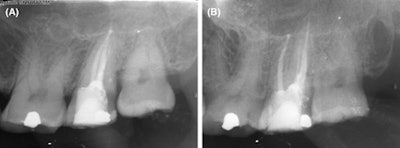

(A) Patient x-ray immediately after surgery. (B) Patient x-ray one year after surgery.

With a clear visualization of the tooth’s canals, clinicians executed the endodontic procedure. About two weeks after the procedure, the patient was asymptomatic, they wrote.